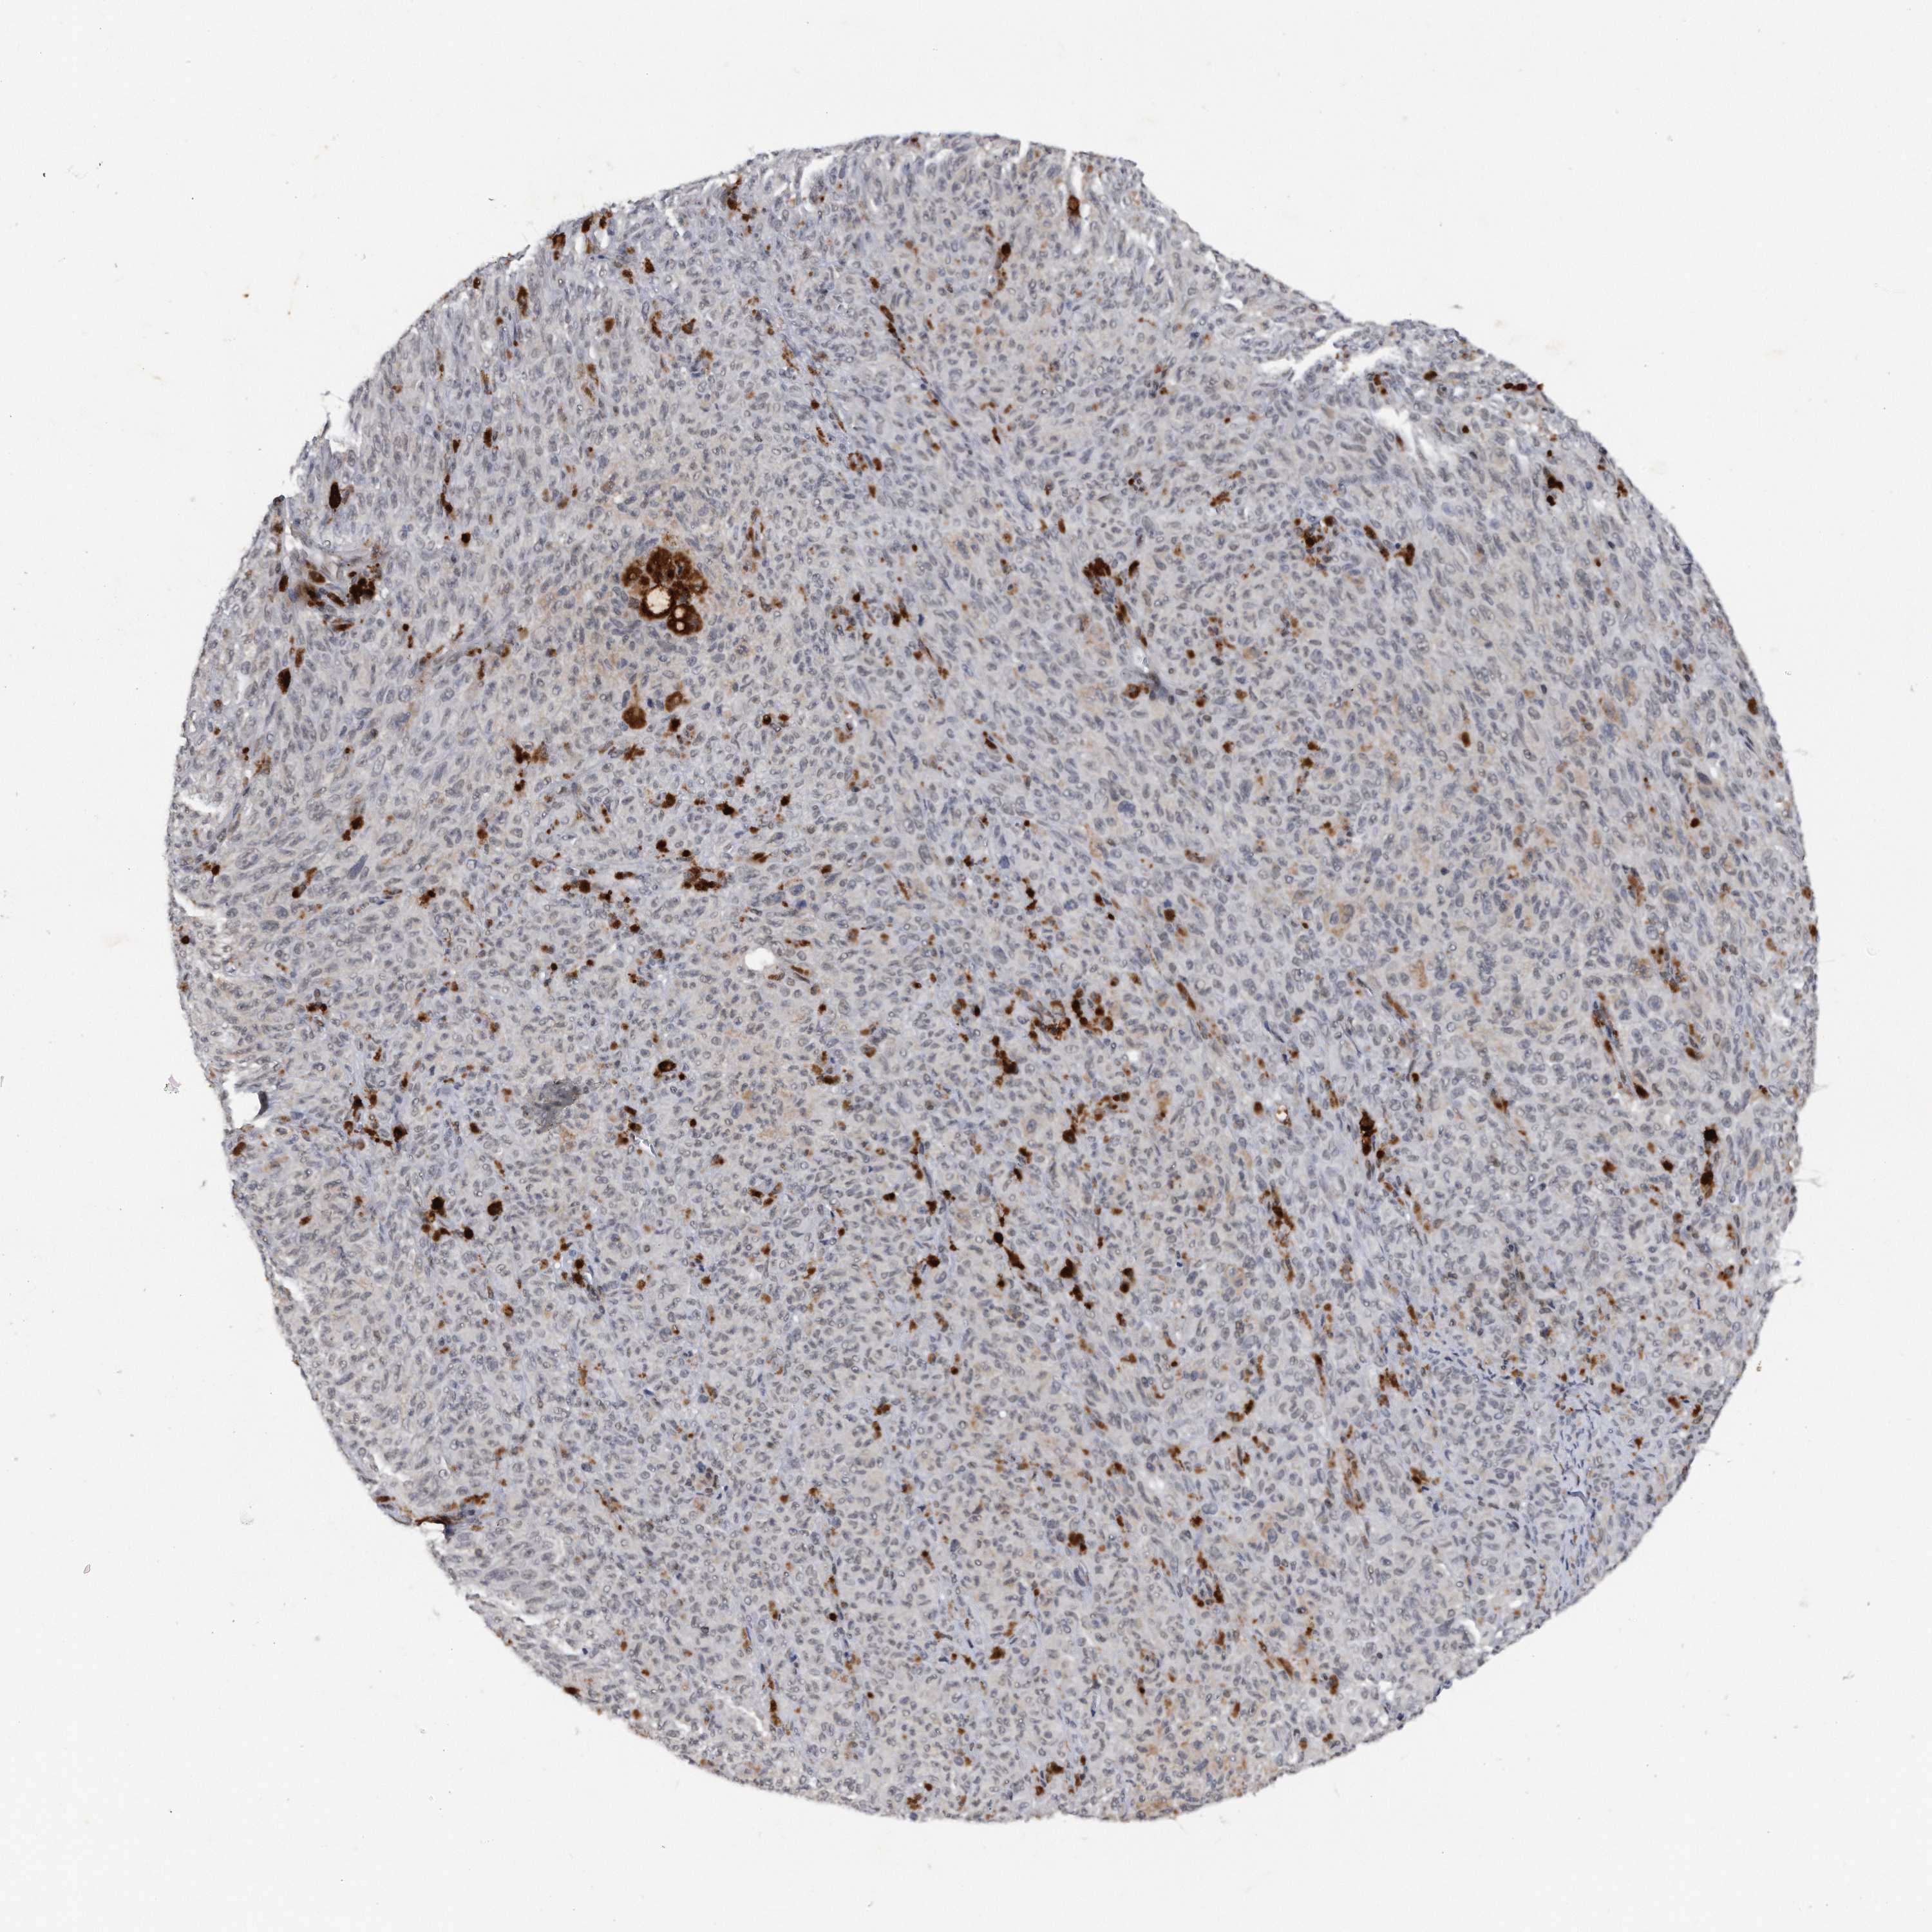

MELANOMA - Protein expressioni

A mouse-over function shows sample information and annotation data. Click on an image to view it in a full screen mode. Samples can be filtered based on level of antibody staining by selecting one or several of the following categories: high, medium, low and not detected. The assay and annotation is described here.

Note that samples used for immunohistochemistry by the Human Protein Atlas do not correspond to samples in the TCGA dataset.

Antibody stainingi

Antibody staining in the annotated cell types in the current human tissue is reported as not detected, low, medium, or high, based on conventional immunohistochemistry profiling in selected tissues. This score is based on the combination of the staining intensity and fraction of stained cells.

Each image is clickable and will lead to virtual microscopy that enables deeper exploration of all samples and also displays staining intensity scores, fraction scores and subcellular localization as well as patient and tissue information for each sample.

Antibody HPA031530

Staining

High

Medium

Low

Not detected

Intensity

Strong

Moderate

Weak

Negative

Quantity

>75%

75%-25%

<25%

None

Location

Nuclear

Cytoplasmic/membranous

Cytoplasmic/membranous,nuclear

Malignant melanoma, NOS

Malignant melanoma, Metastatic site